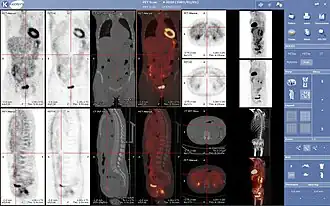

Проекция максимальной интенсивности (MIP) позитронно-эмиссионной томографии (ПЭТ) всего тела у женщины весом 79 кг после внутривенной инъекции 371 МБк 18F-FDG (за один час до измерения).

Нормальная ПЭТ/КТ всего тела с ФДГ-18. ПЭТ/КТ всего тела обычно используется для выявления, определения стадии и последующего наблюдения за различными видами рака.

Аномальная ПЭТ/КТ всего тела с множественными метастазами рака. ПЭТ/КТ всего тела стала важным инструментом в оценке рака.